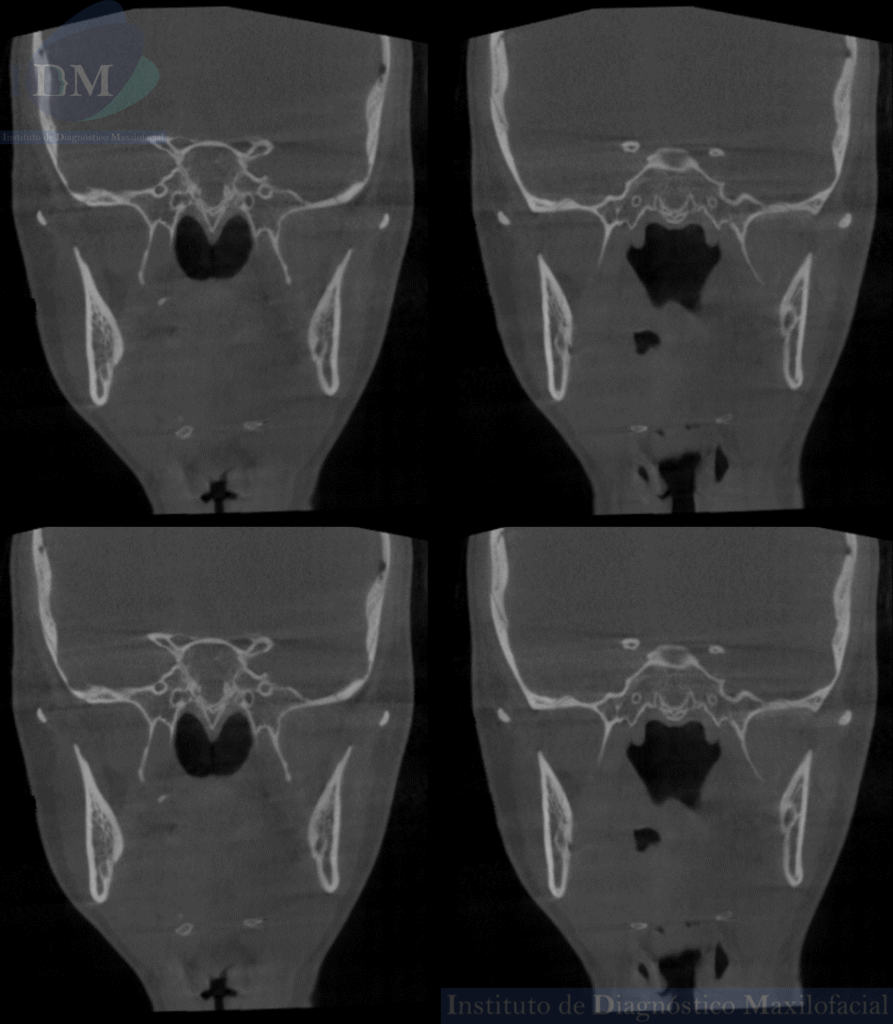

Así mismo en la tomografía volumétrica de haz cónico se evidencia un leve engrosamiento de la mucosa antral de senos paranasales. Siendo lo mas relevante la ausencia de seno esfenoidal en base de cráneo.

CORTES CORONALES